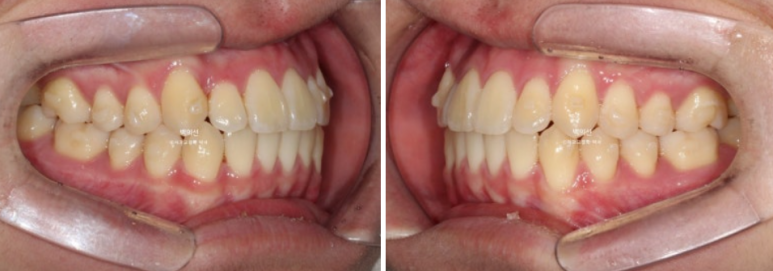

전 후 비교 보겠습니다.

24.04~25.07